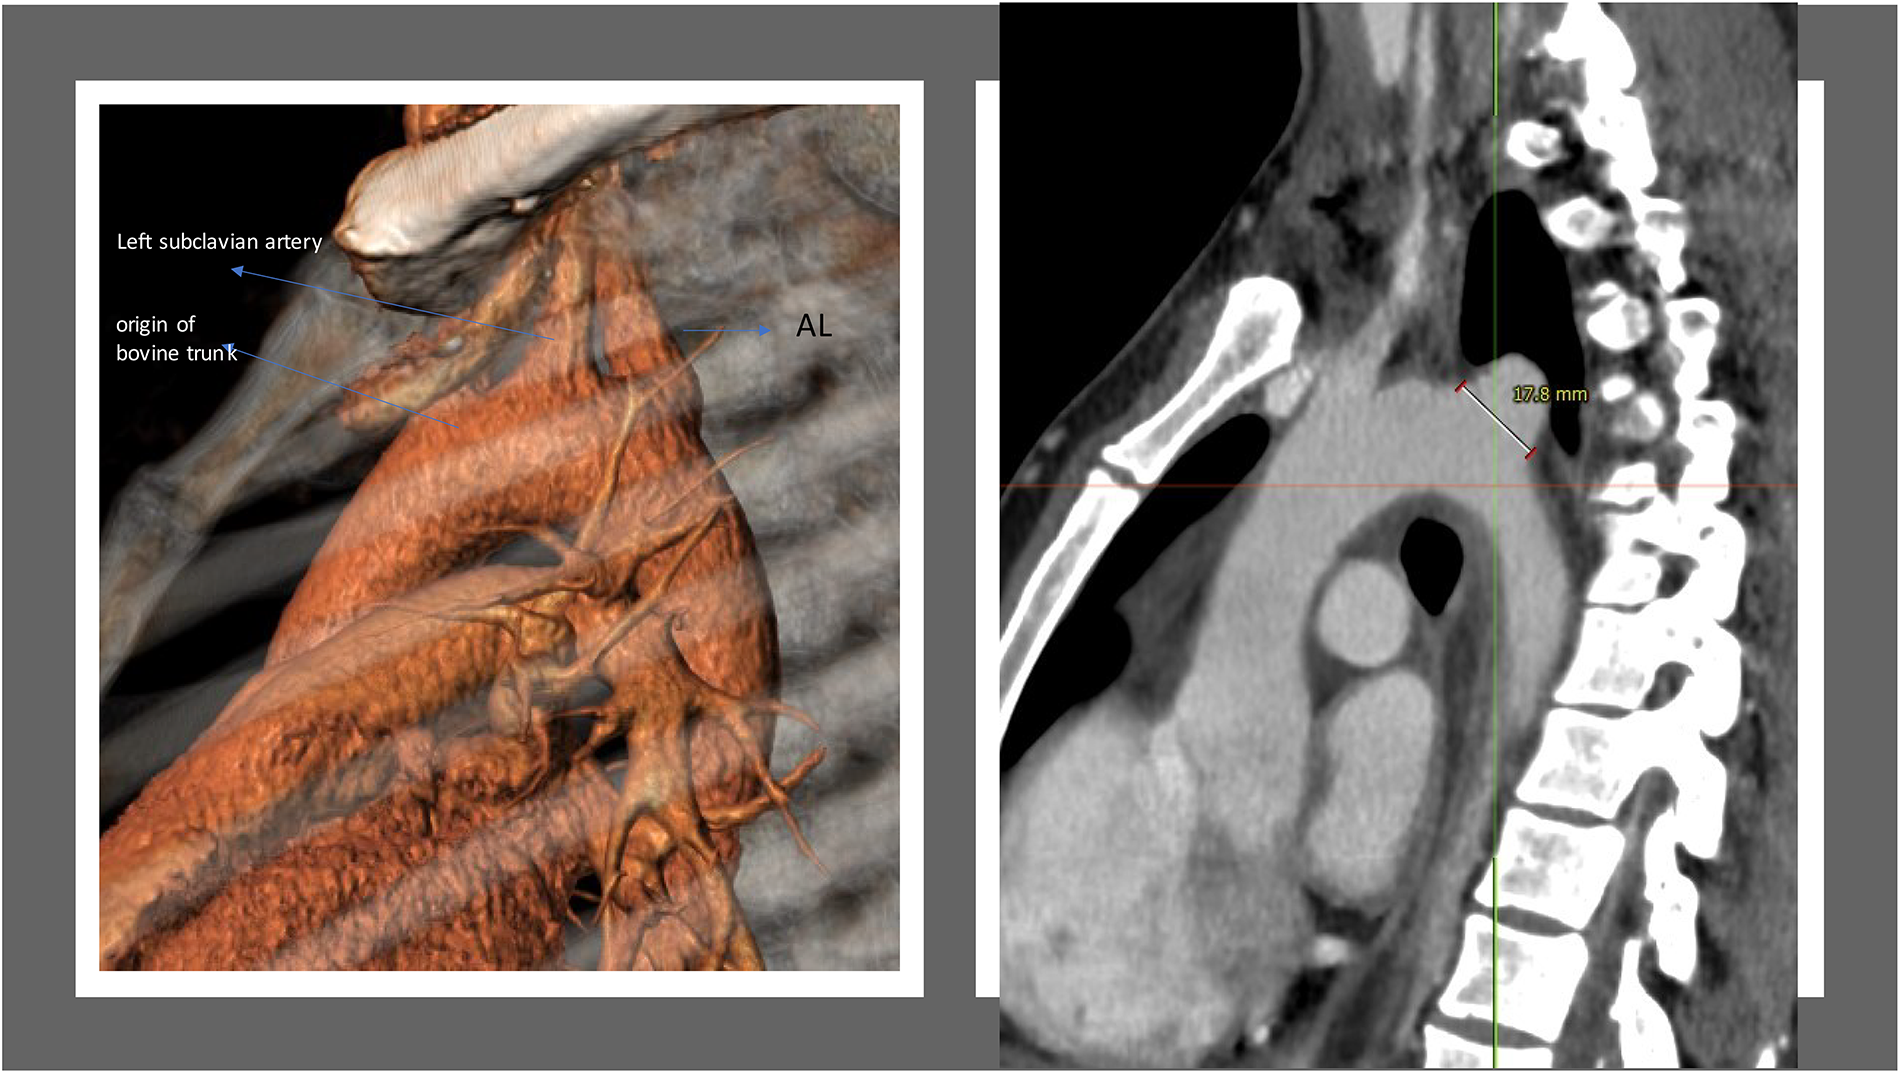

A 44-year-old patient underwent gastric bypass surgery in 2015, resulting in a remarkable weight loss of 30 kg. The patient presented with a progressively worsening dysphagia over the past six months. Diagnostic investigations revealed a pulsatile compression of the esophagus, suggestive of dysphagia lusoria. Subsequent computed tomography (CT) imaging confirmed the presence an aberrant origin of the right subclavian artery from the aortic arch which exhibits ectasia in its proximal portion (Kommerell diverticulum), with a diameter reaching up to 17,8 mm and a retroesophageal course causing compression on the posterior wall of the esophagus. Additionally, there is a presence of a bovine bicarotid trunk, with a 17 mm distance separating it from the subclavian artery. Centerline reconstruction emphasized a narrow 2 mm space between the arteria lusoria and the left subclavian artery (Figures 1, 2). Given the symptomatic nature of the condition and the concurrent presence of Kommerell's diverticulum, surgical intervention was deemed necessary. However, due to the close proximity of the bovine trunk and the arteria lusoria, treatment by TEVAR or hybrid open surgery was considered tedious and relatively at risk.

Figure 1. 3-Dimension reconstruction and sagittal CT scan view revealing an aberrant origin of the right subclavian artery from the aortic arch and a dilated appearance of its proximal segment (17.8 mm), with a retro-esophageal course.

Figure 2. Center line reconstruction imaging by 3mensio medical imaging (utrechtThe Netherlands): It underscores the remarkably proximity between the arteria lusoria and the bovine trunk, measuring a mere 13 mm, alongside the minimal 2 mm separation between the AL and the left subclavian artery.